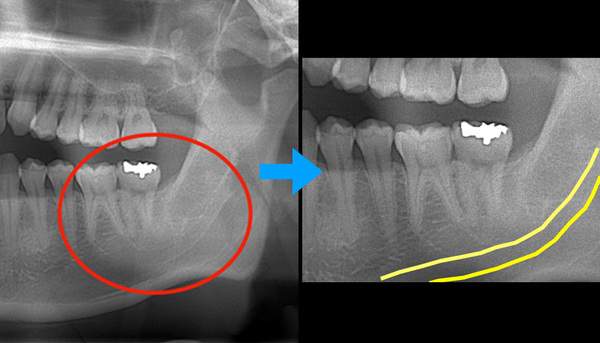

そのため、抜くことをお勧めしていますが、レントゲン写真で、下歯槽神経と親知らずが近接していることが確認できます。

麻布十番歯科で抜歯予定の親知らずの生え方を確認するためのレントゲン写真

CTの画像です。下歯槽神経と親知らずはほんの少し接触していることがわかります。そのため、この親知らずは2回に分けて抜いていくことにしました。1回目は歯の頭の部分だけを切るだけになります。2回目は1−3ヶ月経ってから行います。

1回目で頭の部分を取ったスペースに歯が伸びてきますので、下歯槽神経と離れたかどうかを再びCTで確認して、残りの根の部分を抜いていく方法になります。